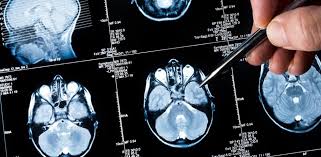

El desarrollo de metástasis, la diseminación de células cancerosas desde el tumor primario a otros órganos o tejidos, es la principal causa de mortalidad por cáncer. Este tipo de recaída distal es cada vez más frecuente en el cerebro, un órgano que se protege de la entrada de tóxicos mediante la barrera hematoencefálica. Esta barrera, sin embargo, también evita que los fármacos penetren en él. Existen tratamientos locales y sistémicos, pero no son beneficios para la mayoría de los pacientes. Manuel Valiente, investigador del Centro Nacional de Investigaciones Oncológicas (CNIO), lidera un equipo que ha decidido dar “una vuelta de tuerca” con una investigación innovadora.

“No estudiamos la metástasis cerebral de acuerdo al tipo de tumor primario que la ha generado, que es como actualmente se hace el manejo de este tipo de pacientes, sino que interrogamos a las propias metástasis cerebrales”, explica Valiente. En los últimos tres años, el grupo ha estado analizando desde un punto de vista genómico las muestras vivas que han ido recibiendo de los 18 hospitales de la Red Nacional de Metástasis Cerebral (RENACER). “Hemos llegado a un sorprendente hallazgo: dentro de los centenares de muestras analizadas encontramos tres perfiles terapéuticos que responderían a una serie de vulnerabilidades específicas que son importantes en el cerebro, pero no quizás en otro órgano”, afirma. Cada uno de estos tres grupos, añade, “respondería a una lista de fármacos concretos”.